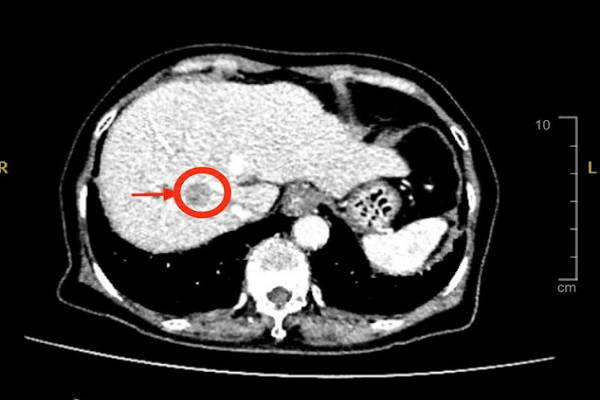

Kết quả chụp MSCT (cắt lớp vi tính) cho thấy, bệnh nhân có khối u gan ở thùy gan phải, kích thước khoảng 2cm, nghi ngờ ung thư gan nguyên phát - Ảnh: BV

Kết quả cho thấy có khối u gan ở thùy gan phải, kích thước khoảng 2cm, nghi ngờ ung thư gan nguyên phát (HCC). Đây là loại ung thư gan thường gặp ở người bị xơ gan, viêm gan B hoặc C mạn tính.